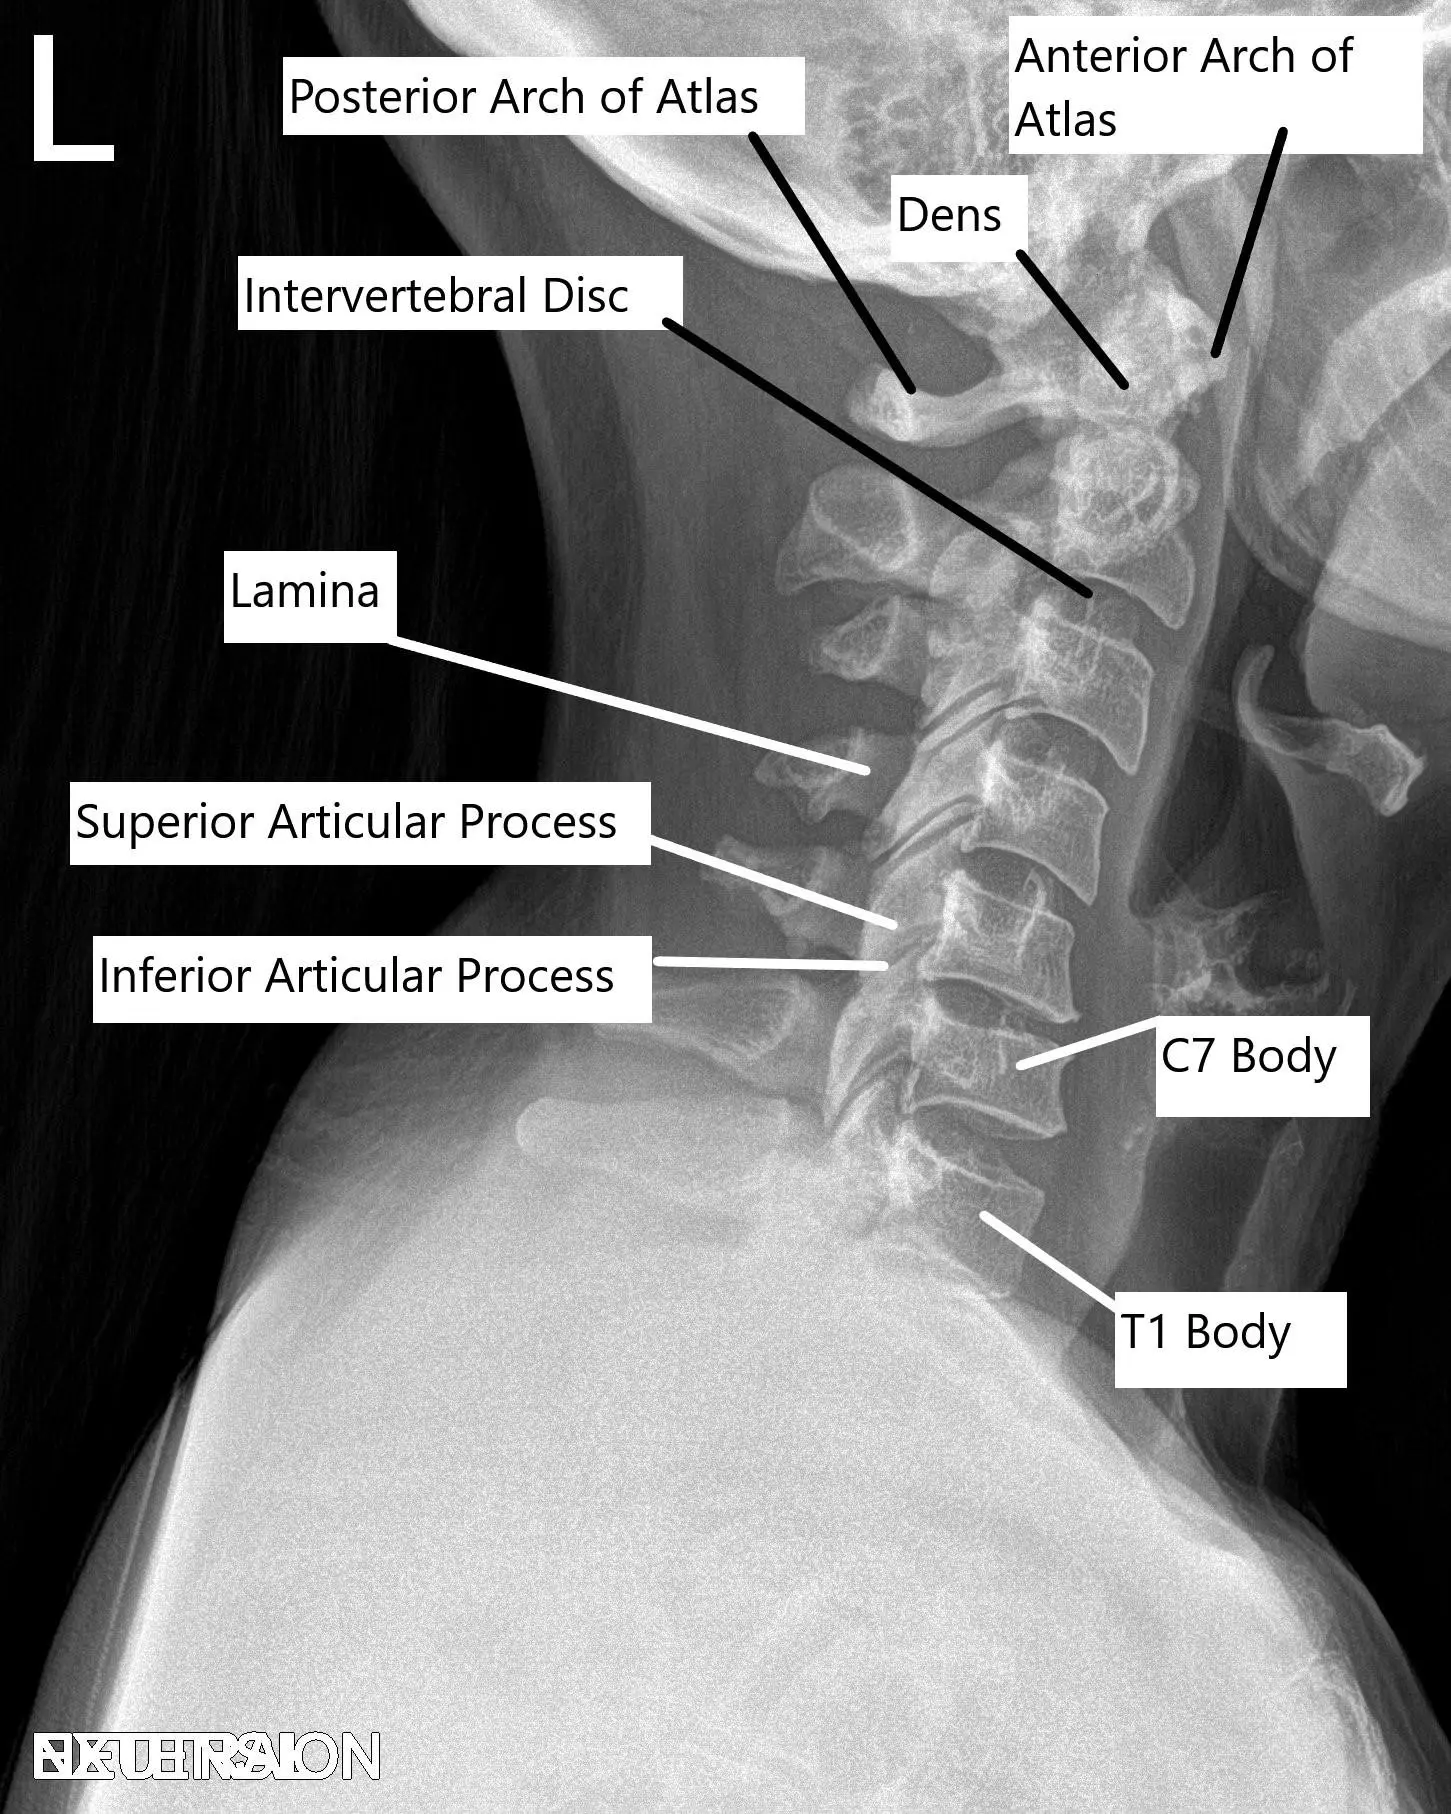

Cervical Spine X-ray in Lateral view.

The cervical spine is composed of seven vertebrae (C1 to C7), which are separated by intervertebral discs. The vertebrae protect the spinal cord and allow for movement in the neck. The foramen, or small openings between the vertebrae, allow spinal nerves to exit the spinal cord and travel to different parts of the body. When these structures become compromised due to degenerative changes, compression can occur, leading to pain and other neurological symptoms.